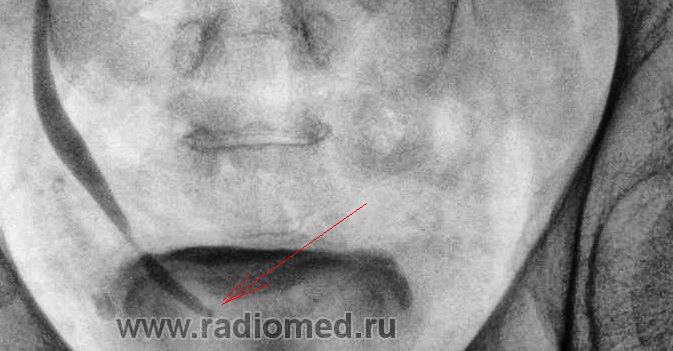

С узистами все ясно - парапельвикальную кисту слева и парапельвикально-каликальную кисту справа они (наверняка) приняли за ампулярного типа лоханки. Но что по КОНКРЕМЕНТУ - в н\трети правого мочеточника на фоне контраста?????

А конкремент-ли это?

Смущает два участка:

1. локальное линейное повышение плотности на фоне контраста (чуть ниже стрелок);

2.коль мочеточник контрастирован на всем протяжении - то в области устья небольшая округлая тень.

На обзорной урограмме рентген-контрастных конкрементов не было выявлено, тут же справа мочеточник законтрастирован на всём протяжении, гипотоничен, если и есть то в проекции устья-возможно.

Вот он "гадёныш" сидит врямо в устье.

Да нет Петрович. Две иллюстрации перед Вашим комментом - это конечно, не камни. Но тень должна быть объяснена.

В данном конкретном случае, констатировано "тугое контрастирование" правого мочеточника на всем протяжении с умеренной эктазией его, по сравнению с левым мочеточником, что является прямым указанием на "наличие препятствия" в дистальном отделе мочеточника, и в частности - в "устье", что и имело место в данном случае. Исследование продолжалось 24 минуты (последний снимок).